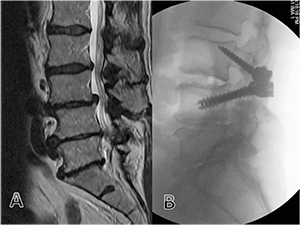

Fig. 5 (A) MRI demonstrating L3,4 low grade spondylolisthesis and

canal stenosis. (B) Fusion L3,4 with MLST technique.